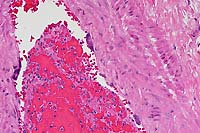

- Case 5-3. Dermis. There is a brisk infiltrate

of neutrophils and eosinophils around, infiltrating, and effacing

the necrotic walls of two parallel arterioles.

- AFIP Diagnosis: Haired skin: Vasculitis and perivasculitis,

necrotizing, neutrophilic and eosinophilic, acute, with multifocally

extensive dermal and subcutaneous hemorrhage, multifocal epidermal

necrosis, and mild epidermal hyperplasia, cross-bred pig, porcine.